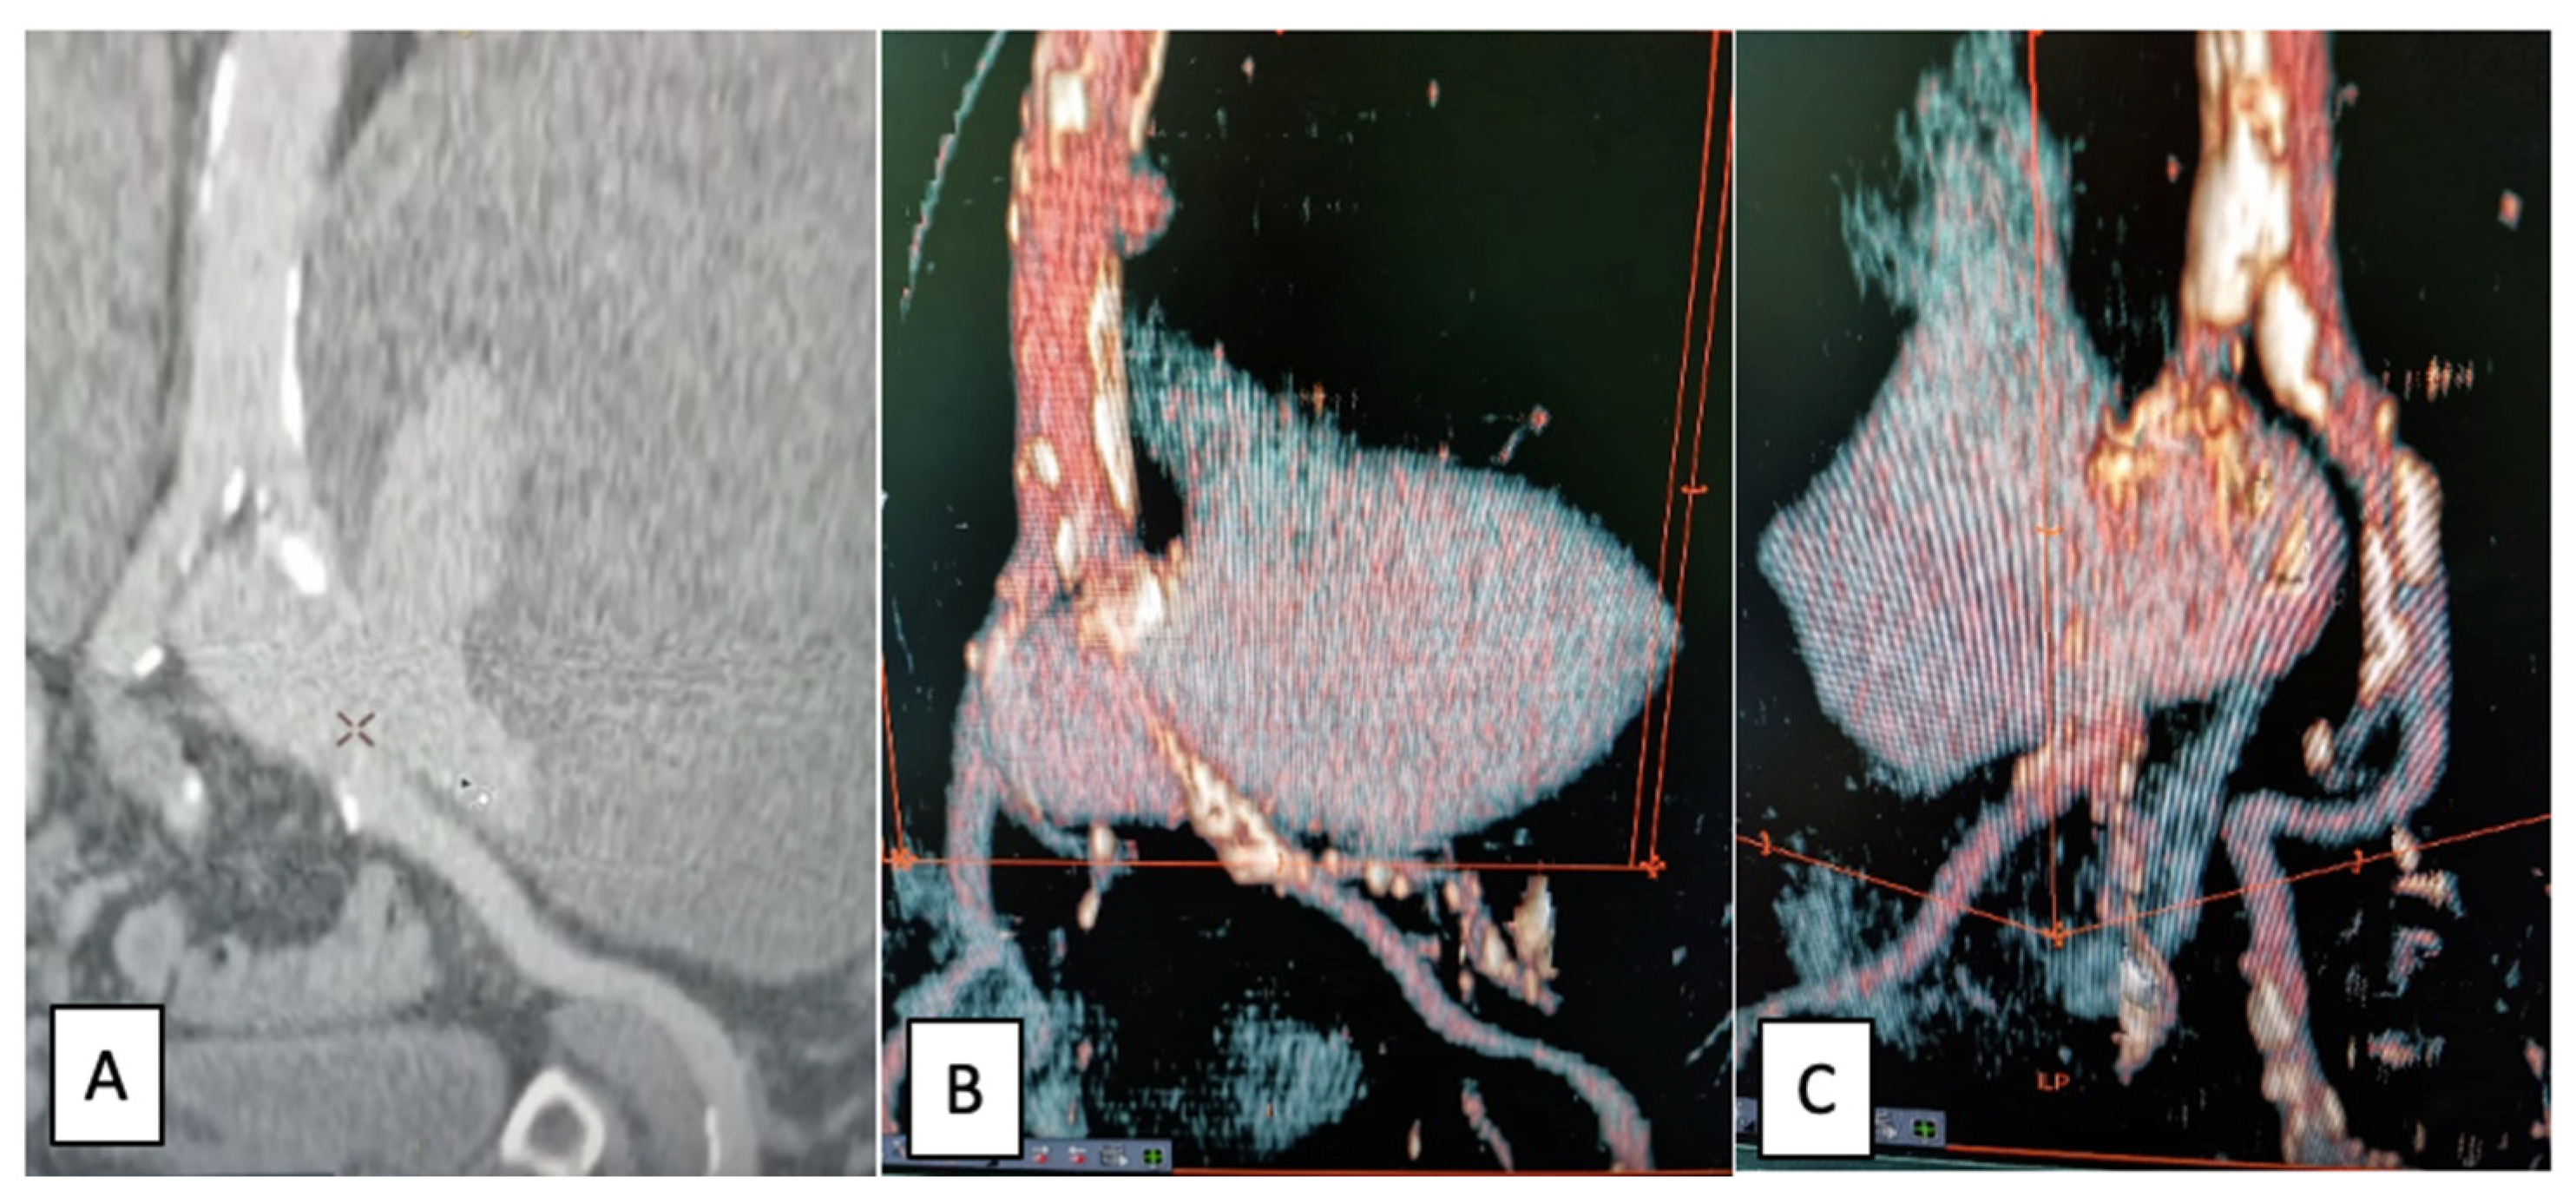

2.1. Case Report I